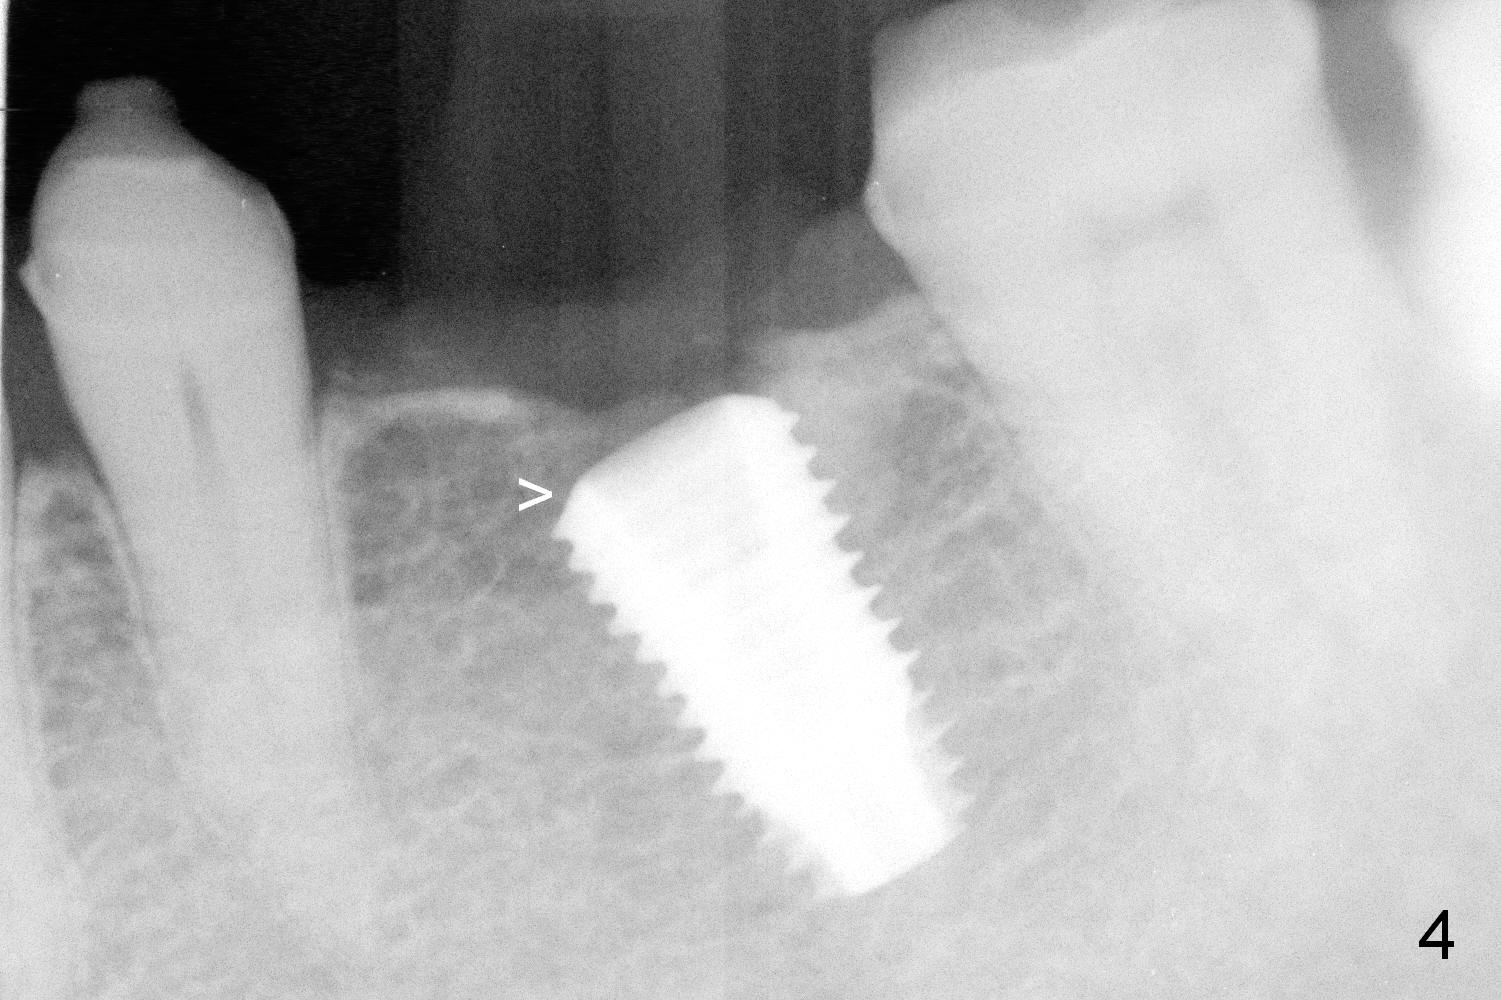

When the patient returns for implant placement, he is pleased to let us know that he has stopped smoking for a week. The edentulous ridge at #19 looks wide (Fig.1). The tooth #3 is supraerupted, while there is no clearance between the abutments (#18 and 20) and the opposing dentition (Fig.2). After incision, the ridge is confirmed to be wide with the aid of implant positioners. The bone is felt soft during initial osteotomy (Fig.3). Attention is being paid to correcting the trajectory. Under prep is ignored. When a 5.9x10 mm implant is placed, the insertion torque is between 25 and 30 Ncm (Fig.4).

Since the implant is placed subcrestal mesially (Fig.4 >), the mesial margin of the abutment (5.8x4(3) mm) is subgingival (Fig.5 ^). An immediate provisional has to be made to keep the gingiva from growing into the margin. After occlusal clearance (Fig.6), the immediate provisional is seated (Fig.7). There is no paresthesia postop.